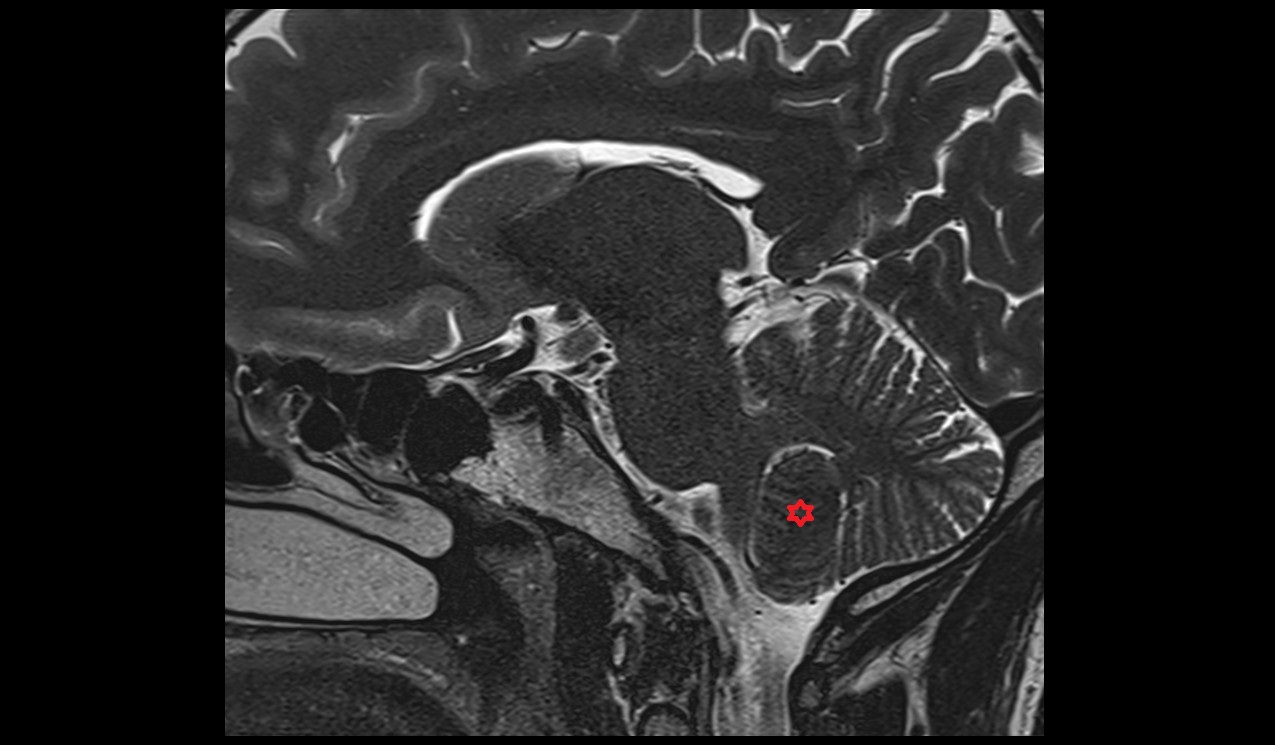

- Cerebellum

- Cerebellar tonsil (H IX)

- Culmen (IV, V) of Cerebellum

- Declive (VI) of Cerebellum